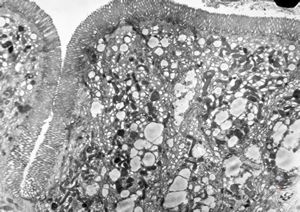

jejunum … lipid malabsorption

duodenum … lipid malabsorption